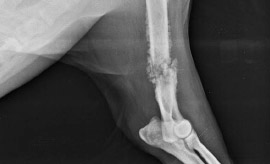

Boomer, macho chowmix de 8 años se presenta con:

• Cojera miembro derecho anterior durante 3-4 semanas.

• Inflamación tejidos blandos circundantes.

• Dolor a la palpación del cúbito.